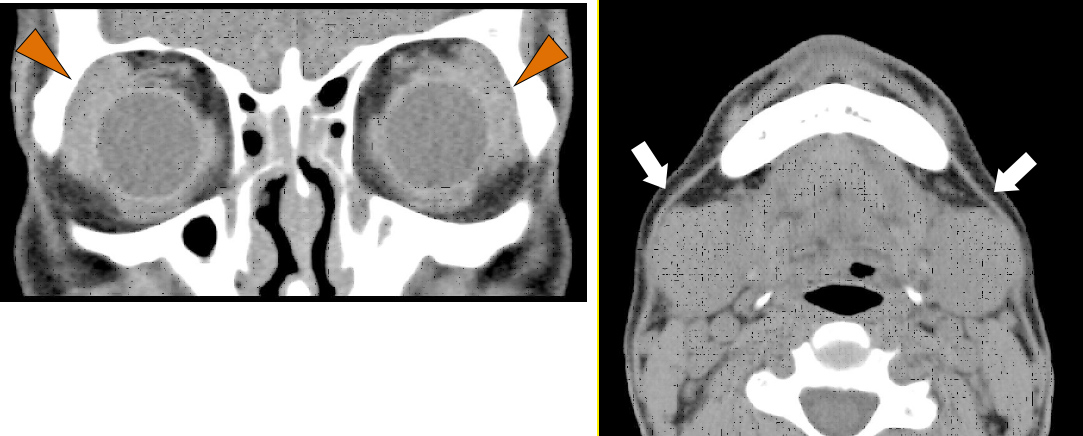

IgG4関連涙腺・唾液腺炎の女性。CTでは両側の涙腺腫大(矢頭)と顎下線腫大(矢印)がみられる。

②画像診断としては, CTやMRI,エコー検査が用いられ,涙腺・唾液腺の腫れの確認と,全身にIgG4関連疾患のほかの病変がないかどうかをチェックします.なお,まだ保険適用はありませんが,FDG-PET検査では感度高く,IgG4関連疾患の病変を検出できることが報告されており,今後の保険適用が期待されます.